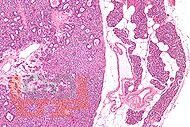

Клиническая анатомия и патология околощитовидных желез

В учебно-методическом пособии кратко изложены сведения об анатомии

паращитовидных желез, фосфорно-кальциевом обмене. Пациенты с первичным

гиперпаратиреозом занимают третье место в патологии эндокринных органов и

встречаются у разных специалистов: эндокринологов, онкологов, травматологов,

урологов. При этом знание смежных специалистов данной патологии, имеющей

многогранные клинические проявления, оставляет желать лучшего. Отсутствие

должной настороженности и понимания нарушений фосфорно-кальциевого обмена

приводит к поздней диагностике гиперпаратиреоза и фатальным клиническим

ошибкам.